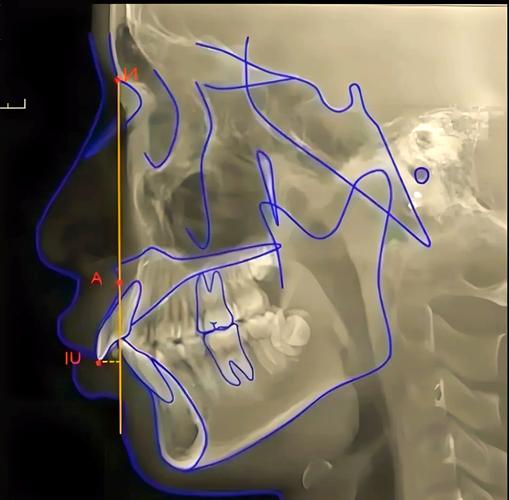

面轴角的测量需依赖特定的解剖标志点及参考平面,常用解剖标志点包括:鼻根点(N,鼻额缝的最前点)、鼻下点(Prn,鼻小柱与上唇的连接点)、软组织颏前点(Pos,颏部软组织最前点)、眶耳平面(FH平面,由眶下缘最低点与外耳道上缘构成的平面,作为颅部参考基准),面轴角的核心定义是面部轴线与FH平面的夹角,其中面部轴线通常由鼻根点至颏前点(N-Pos连线)构成,反映面部中下份的整体倾斜度。

根据测量范围,面轴角可进一步细分为整体面轴角(N-Pos与FH平面的交角)、面中份轴角(N-Prn与FH平面的交角)及面下份轴角(Prn-Pos与FH平面的交角),不同角度的组合分析可明确面部不调的具体部位(如面中份过长/过短、面下份后缩/前突等)。

(图片来源网络,侵删)- 头颅侧位片:患者取自然头位(眶耳平面与地面平行),拍摄标准头颅侧位片,需校准放大率(通常放大率不超过10%)。

在侧位片或三维模型上,由两名正畸医师独立标记关键标志点(N、Prn、Pos、FH平面),取平均值以减少误差,FH平面的确定需严格依据眶下缘最低点与外耳道上缘。 -

- 传统方法:使用透明量角器在侧位片上直接测量N-Pos与FH平面的夹角,或通过头影测量软件(如Dolphin、Vceph)进行数字化计算。